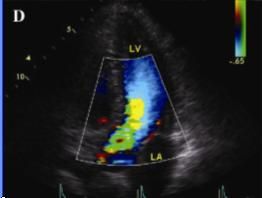

糖尿病性腎病Ⅴ期:腎功能衰竭期。糖尿病病人一旦出現持續性尿蛋白發展為臨床糖尿病腎病,由於腎小球基底膜廣泛增厚,腎小球毛細血管腔進行性狹窄和更多的腎小球荒廢,腎臟濾過功能進行性下降,導致腎功能衰竭,最後病人的GFR多<10mL/min,血肌酐和尿素氮增高,伴嚴重的高血壓、低蛋白血症和水腫。病人普遍有氮質血症引起的胃腸反應,如食慾減退、噁心嘔吐,並可繼發貧血和嚴重的高血鉀、代謝性酸中毒和低鈣搐搦,還可繼發尿毒症性神經病變和心肌病變。這些嚴重的合併症常是糖尿病腎病尿毒症病人致死的原因。

3.晚期並發心血管多種疾病如動脈硬化、心包炎、結腸炎、出血性疾病及神經系統病變。

(1) 長期血透:從20世紀60年代初期就已開始對晚期糖尿病腎病病人套用透析治療,近年來接受血透者有所增加。如1972年還不到0.5%,1981年上升到7.3%,根據1988年美國統計因糖尿病腎病腎功能衰竭接受血透者約為新血透病人的28%。但由於終末期糖尿病腎病除腎臟病變外,幾乎同時都合併有其他器官的血管合併症,特別是由於全身性小動脈硬化,血管壁僵硬,血透的血管通道難以建立,動靜脈瘺管在糖尿病人保留的時間明顯短於非糖尿病人。因此,糖尿病腎病病人血透的存活率,儘管過去10年有了改善,但仍低於非糖尿病人,據Matson與Kjellstrand對369例長期血透病人的隨訪分析,3年累積存活率為45%,5年25%,10年為9%,年齡在60歲以下的1型糖尿病腎病病人血透的存活率20世紀80年代較之60年代有了明顯的提高,1年存活率由60%上升為85%,3年存活率由30%上升為60%,5年存活率由12%上升到45%。但Jacobs等報導歐洲1098例第1年存活率為67%,第2年為49%。1型糖尿病血透病人的死亡率幾乎為非糖尿病人的2.5~3倍,死亡原因仍以心血管合併症為主占51%,其次為中止透析占24%,感染占14%,其他如電解質紊亂(高鉀或低鉀)、高滲性昏迷等約占11%。血透的預後與糖尿病類型有關,1型病人的存活時間明顯短於2型病人,但2型病人有心血管合併症者存活時間短;病人年齡>60歲者預後差,60歲以下則差別不大;至於是否合併有糖尿病視網膜病變對預後關係不大。